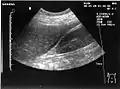

Ultrasonographic view of the abdomen demonstrating fluid within Morison's pouch